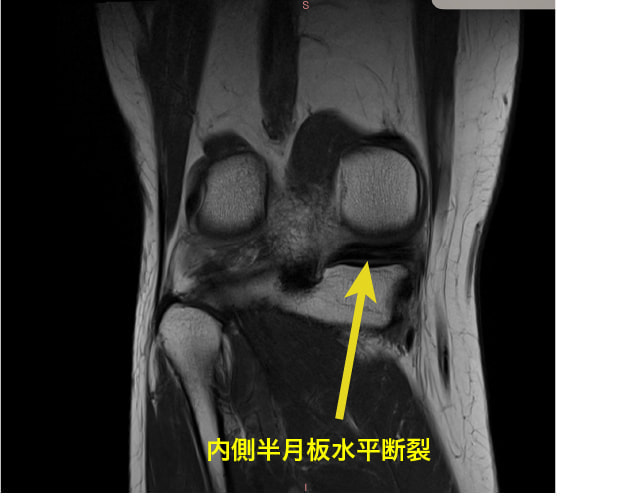

上記に紹介している膝のMRIは変形性膝関節症の原因の1つとして指摘されている、「内側半月板後根(後節)損傷MMPRT」の一症例です。

膝関節の方面のCOR画像(前額面)ですが、内側半月板の水平断裂が見られます。